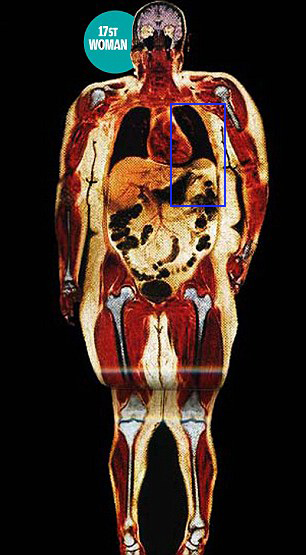

Images with red objects have the red object as the heart. Of note, the sternum does not completely cover the heart, the intercostal spaces are greater than the ribs, and on the silhouette, the heart is 9.52% of the boxed area.